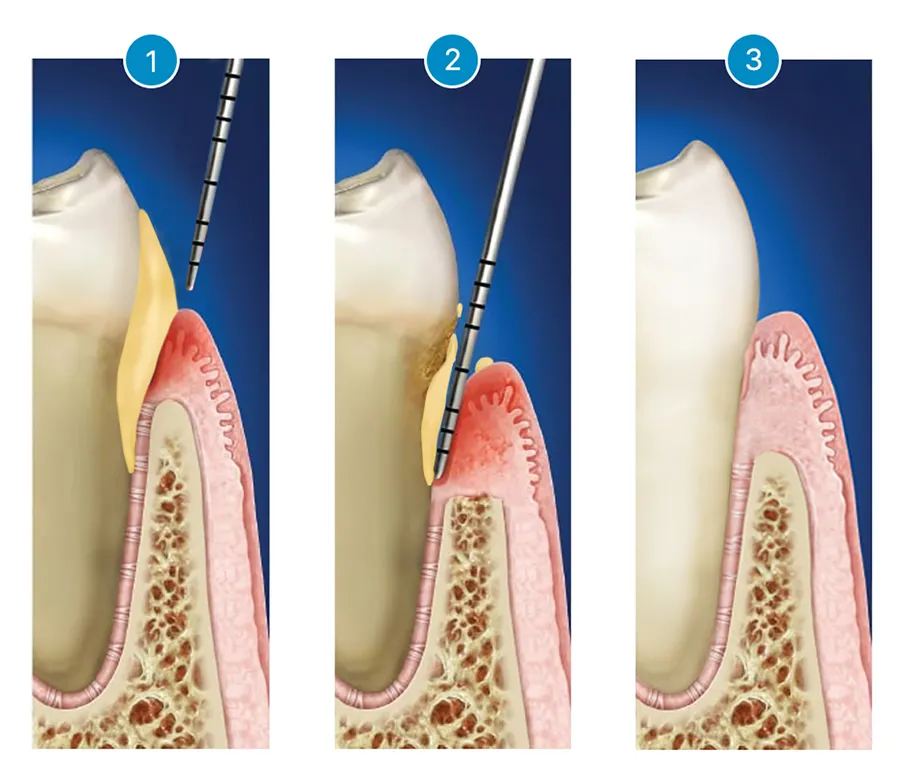

一方、ルートプレーニングは、上の写真のように「歯周掻爬術」または「歯肉縁下掻爬術」とも呼ばれ、目に見えない歯と歯茎の境界面「歯肉溝」にたまった歯石を除去する方法です。歯根面を滑らかにし、再付着を促進することを目的としています。

ルートプレーニングは、上の例のように目に見えない部分にたまった炎症や歯石を取り除くために、歯茎の深い部分まで治療器具を使うため、どうしても痛みが発生します。そのため、ルートプレーニングは通常、局所麻酔をして行われますが、